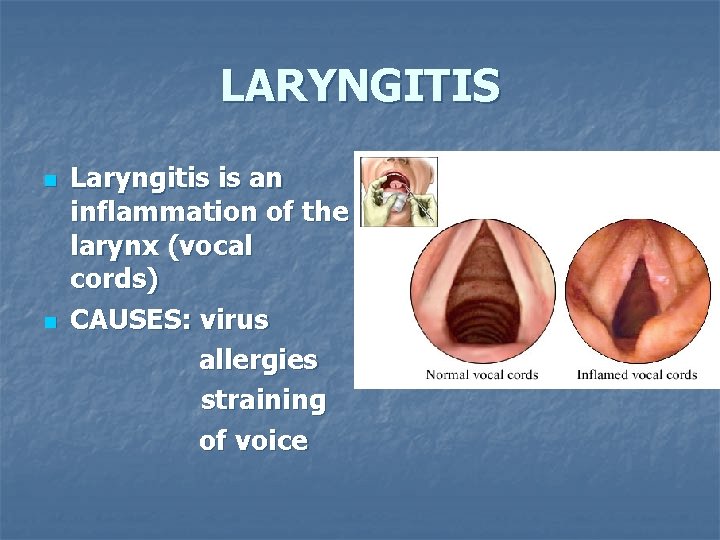

LARYNGITIS n n Laryngitis is an inflammation of the larynx (vocal cords) CAUSES: virus allergies straining of voice

LARYNGITIS n n When the larynx is inflamed, the vocal cords can’t vibrate properly – therefore the voice is hoarse or even non-existent TREATMENT – rest, fluids, no talking!!